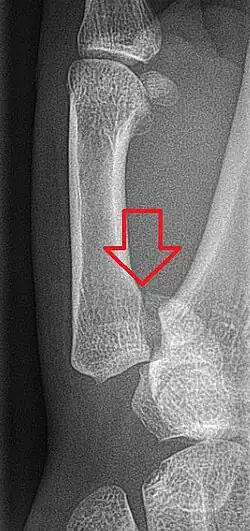

Fratura de Bennett

Fratura de Bennett é uma ruptura da base do polegar, mais especificamente da primeira articulação carpo-metacarpal, formada pela epífise proximal do primeiro metacarpo e pelo osso trapézio. É o tipo mais comum de fratura do polegar, pode ser causado por queda sobre mão aberta ou ao golpear contra um objeto duro. Essa fratura intra-articular é quase sempre acompanhada por algum grau de deslocamento dos ossos (luxação) da articulação carpometacarpiana (CMC).[1]

Diagnóstico

Se há 3 signos clínicos de fratura deve-se pedir uma radiografia de mão, frente e perfil.